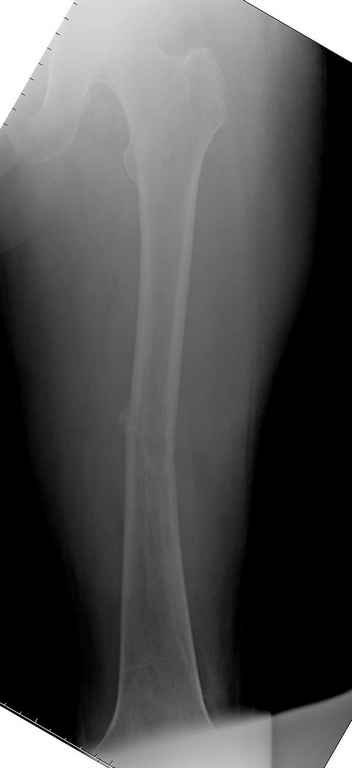

Здесь случай 66 летней пациентки со спонтанными болями в левой нижней конечности, обратилась в приемное, сделаны снимки бедра и КТ.

Патологический перелом бедра, конечность на вытяжении.

Со слов, больная ничем не болела, только последние 3 месяцев чувствовала боли в бедренной области. КТ брюшной полости подтвердил увеличенную правую почку. (5-6)

Для предупреждения кровотечения во время рассверливания, за день до операции провели эмболизацию сосудов питающий метастаз. http://radiology.rsnajnls.org/cgi/reprint/150/3/673.pdf (7-11, 12-15-16)